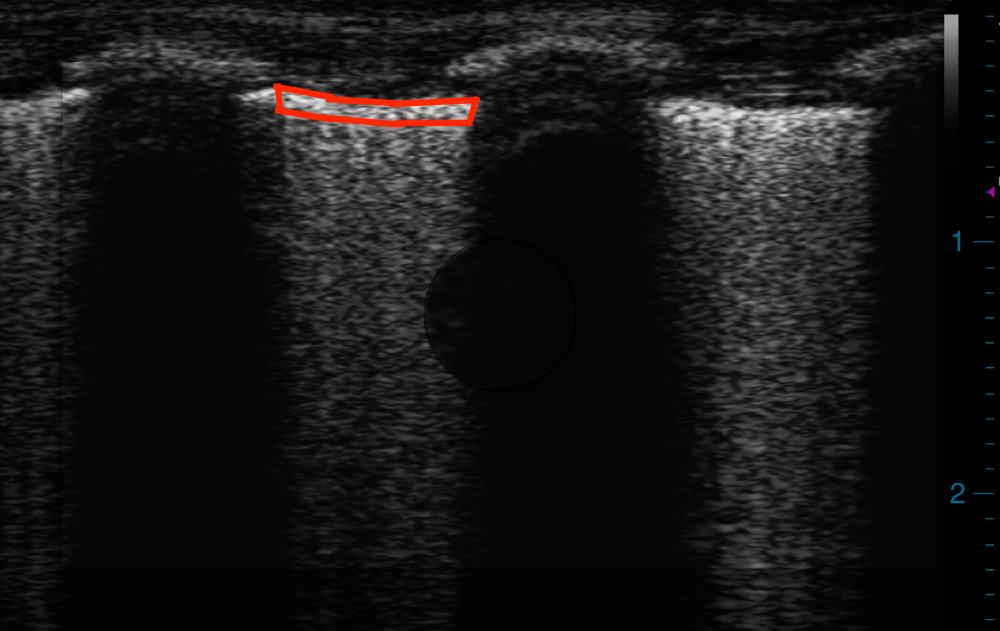

Fig. 1: ROI (red tracing) for measurement of Q-LUSMGV.

The ROI was delineated by (1) superior margin defined by the pleural surface; (2) lateral margin defined by the rib shadows; and (3) inferior margin defined by a depth of 50 pixels corresponding to one millimetre in depth. Q-LUSMGV; quantitative lung ultrasound mean grey value.